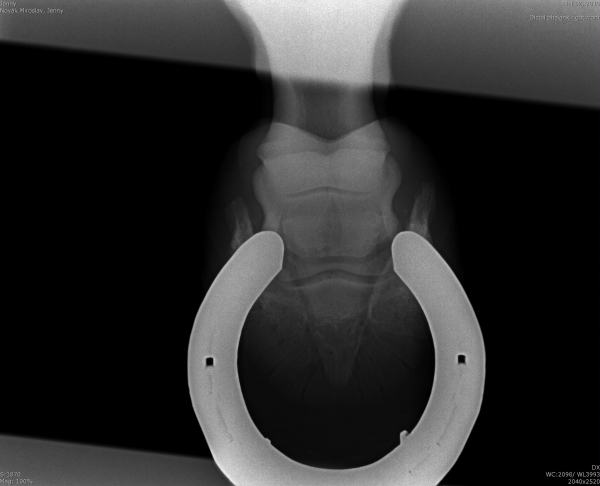

Chronicky schvácené kopyto

Podotrochleóza

Sam - kladrubský hřebec s laminitídou a výhřezem kopytní škáry, teď krásně chodící a to hlavně díky velké pomoci podkováře, p.Schmidta